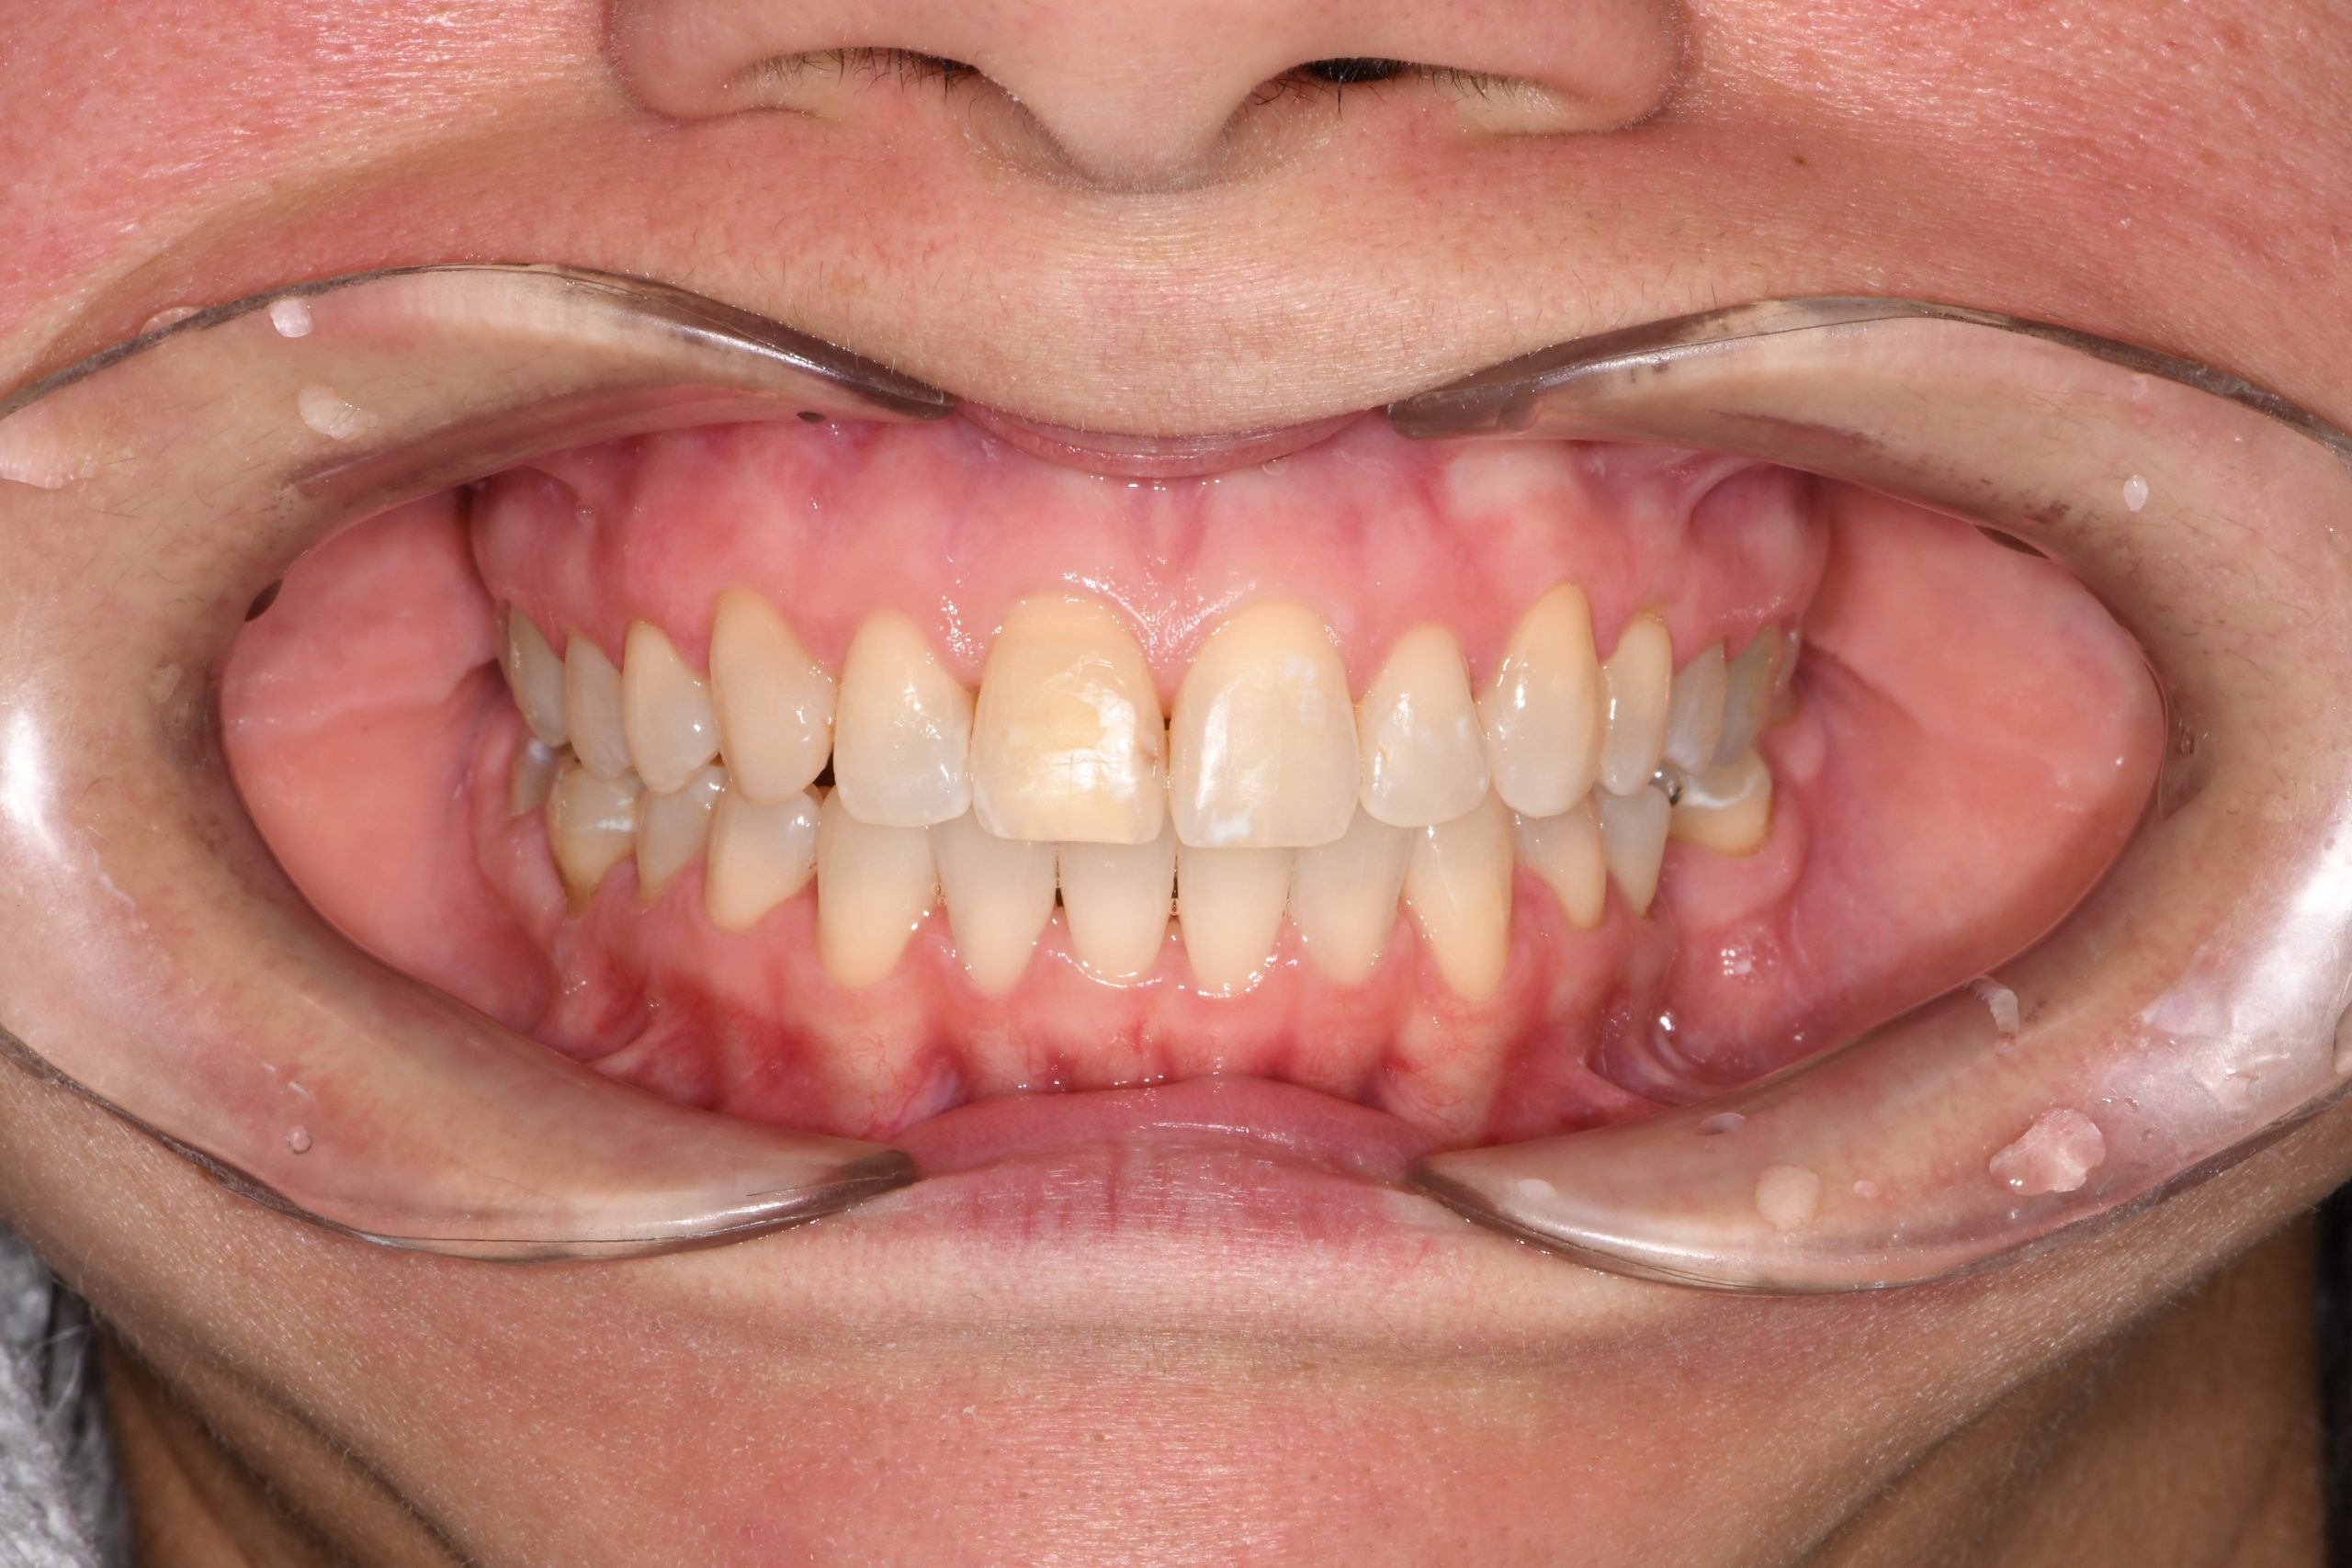

Az elmúlt évekből rengeteg szakmai referenciát tudnánk bemutatni, amelyek különböző fogszabályozási problémákat oldottak meg. Válogatva a több száz esetből, ezen az oldalon olyan képeket, információkat igyekeztünk bemutatni, amelyeknek a segítségével a jövőbeni pácienseinknek azt tudjuk üzenni: A Te fogsorod is lehet gyönyörű!

(Képeket a Pácienseink külön írásos beleegyezésével mutatjuk be!)